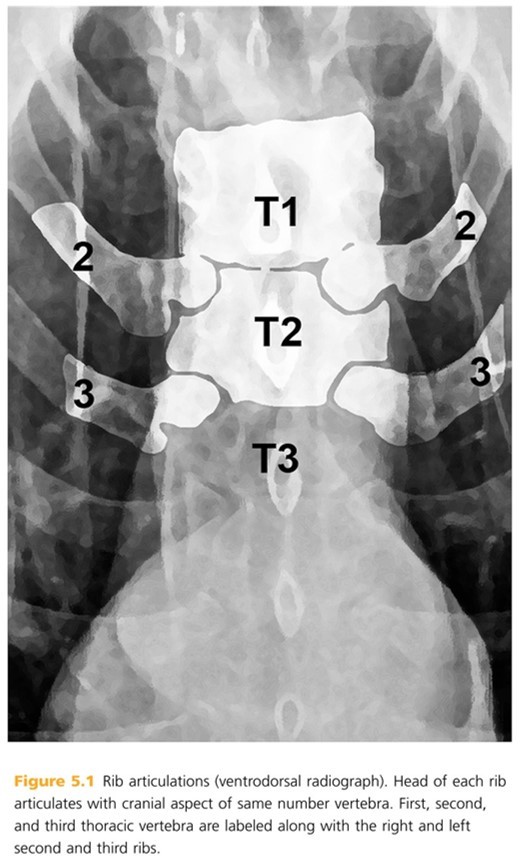

Ribs are typically numbered 13 pairs with head of each rib articulating with cranial aspect of _____ _____ _____.

same numbered vertebra